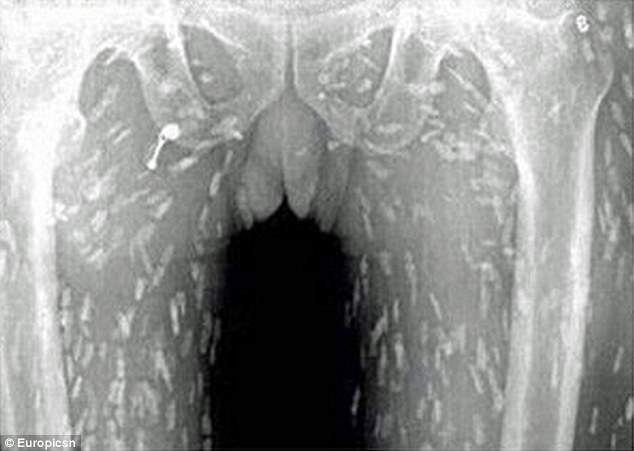

▼醫生提醒民眾,吃生魚片、生豬牛肉都可能感染,一些魚塘的淡水魚更加危險。因為魚塘裡的魚很容易被污染,沾上糞便。感染絛蟲後非常麻煩,如果這些絛蟲在肌肉外圍,只要驅蟲就能解決問題。如果已經侵入腦部,就可能變成腦囊蟲病,最後引發腦水腫,還會危及生命。

▼下面這位醫生展示了恐怖的絛蟲。